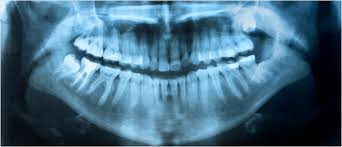

V tokratni Secundi Conversatio gostimo dr. dent. med. Damirja Škripca, ki je v Sloveniji oral ledino na področju laserskega zobozdravstva. Naš cenjeni gost med drugim že vrsto let opozarja na problem amalgamskih plomb in toksičnosti fluora. O tem, kaj je biološko zobozdravstvo in zakaj je potrebno za neboleče puljenje zob obvladati met kladiva, pa več v oddaji.